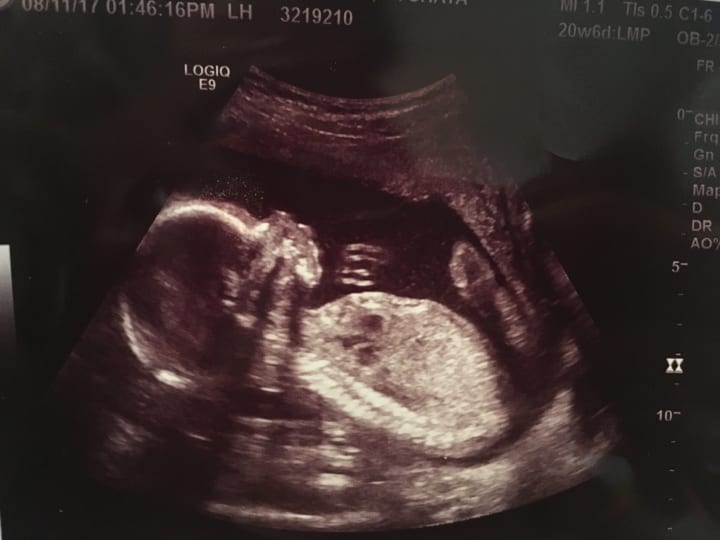

Times goes by, I’m being rushed to the emergency room.. something is not right! Praying my baby boy would be alright. Oh did I forget to mention I was five and half months pregnant? My sister stayed there with me the whole time.